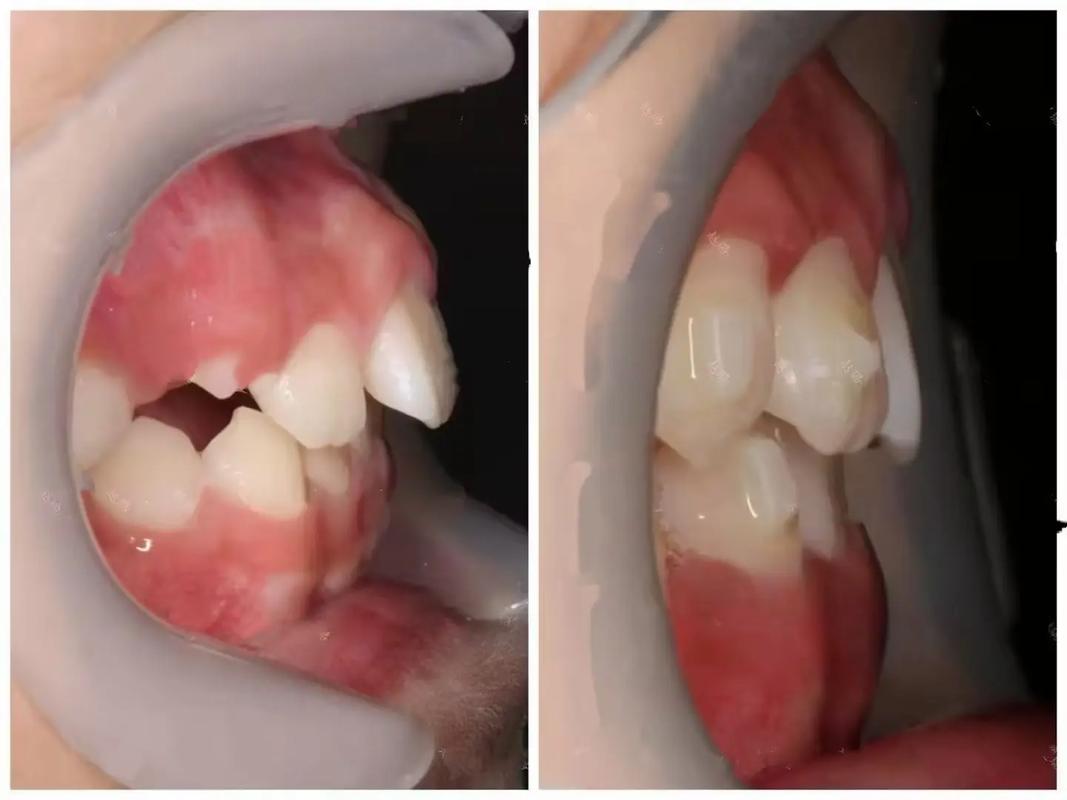

牙外突是常见的牙齿畸形问题,表现为牙齿在唇侧过度突出,不仅影响面部美观,还可能导致咬合功能障碍、发音问题,甚至增加口腔清洁难度引发牙周疾病,随着正畸技术的发展,牙外突矫正已不再困难,通过科学方案可有效改善牙齿排列与面部轮廓,恢复口腔健康与自信。

牙外突的形成通常与多种因素相关,遗传因素是重要原因,若父母存在牙颌畸形,子女出现牙外突的概率更高;不良口腔习惯,如儿童时期的吮指、咬唇、口呼吸、吐舌等,会持续对牙齿施加异常力量,推动牙齿向前移位;替牙期障碍,如乳牙早失导致邻牙移位、恒牙萌出空间不足,也可能造成牙齿拥挤外突;腺样体肥大等呼吸道疾病导致的长期口呼吸,会使上颌骨发育过度、下颌骨后缩,加剧牙外突程度。

牙外突的影响不仅限于美观,从功能角度看,严重的牙外突会导致上下牙齿咬合关系紊乱,咀嚼效率降低,长期可能引发颞下颌关节紊乱;从健康角度看,突出的牙齿更容易受到外力撞击,且牙缝间易堆积食物残渣,增加龋齿和牙龈炎风险;从心理层面看,牙外突可能影响个人社交自信,尤其对青少年而言,容易产生自卑心理。